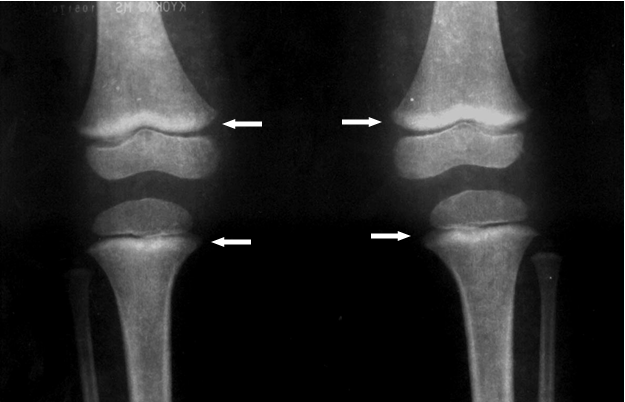

1.La opción correcta es C. La mejor prueba para confirmar la intoxicación por plomo es medir el nivel de plomo en la sangre venosa. Comentarios para la A. La mejor opción es C. La mejor prueba para confirmar la intoxicación por plomo es medir el nivel de plomo en la sangre venosa. Protoporfirina eritrocitaria (PE), comúnmente analizada como protoporfirina zinc (ZPP), no es suficientemente sensible a bajos niveles de plomo en la sangre. Comentarios para la B. La mejor opción es C. La mejor prueba para confirmar la intoxicación por plomo es medir el nivel de plomo en la sangre venosa. Las extracciones de sangre capilar pueden no ser exactas. Comentarios para la C. Correcto. La mejor prueba para confirmar la intoxicación por plomo es medir el nivel de plomo en la sangre venosa. Comentarios para la D. La mejor opción es C. La mejor prueba para confirmar la intoxicación por plomo es medir el nivel de plomo en la sangre venosa. Las radiografías abdominales pueden ser útiles en casos de altos niveles de plomo en la sangre, para descartar la ingestión de un objeto que contenga plomo. |